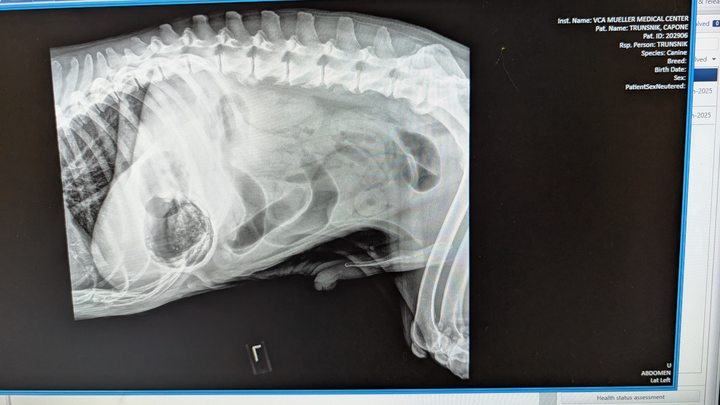

Hello, my name is Destiny and my fiance's name is Natasha she goes by Tasha we are in need of help raising funds to get surgical treatment for our very beloved CAPONE he's our 12 year old senior American Bulldog he's my fiance's BEST FRIEND LITERALLY. Her main man! Everyone who's met Capone falls in love he's just the sweetest boy you could ever meet! A while ago he started acting extremely lethargic, not eating, not sitting down and not very alert at all.. We took him to the vet and they have charged us $1,500 for X-rays and blood work to find that he has a blockage in his stomach and we desperately need help to save him and get him into surgery! Please, if you find it in your heart to help in any way we would greatly appreciate it. My birthday is also tomorrow 05/31 this would be the best birthday gift!! <3 I couldn't imagine not saving him.